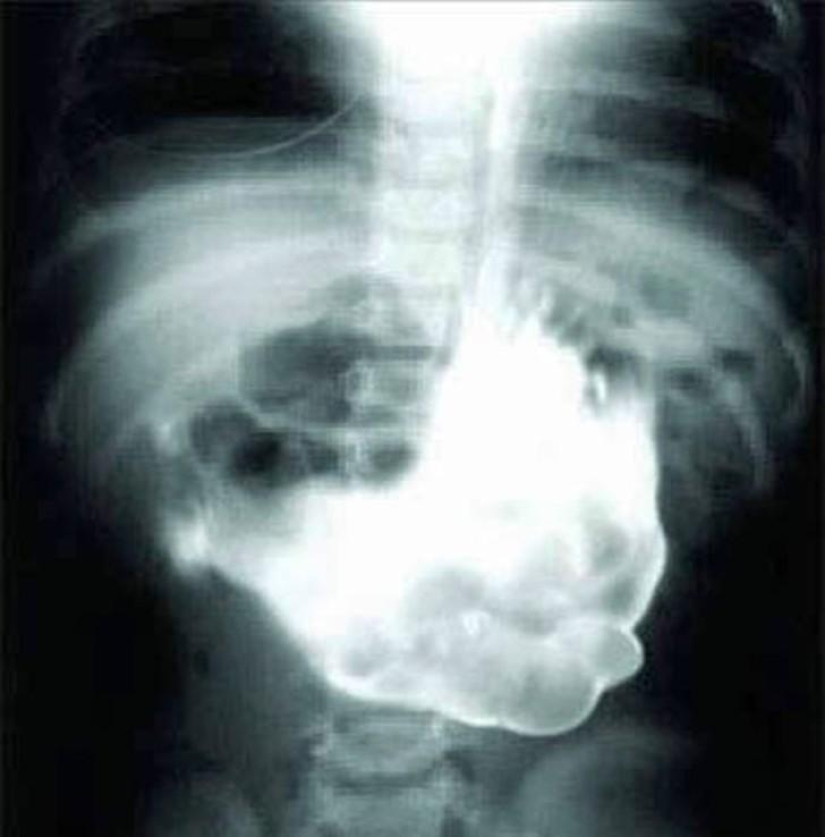

Cutlery.